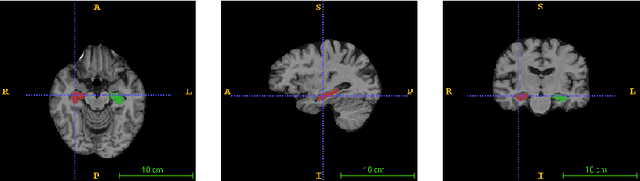

Abstract:Purpose: Advancements in MRI Tissue Phase Velocity Mapping (TPM) allow for the acquisition of higher quality velocity cardiac images providing better assessment of regional myocardial deformation for accurate disease diagnosis, pre-operative planning and post-operative patient surveillance. Translation of TPM velocities from the scanner's reference coordinate system to the regional cardiac coordinate system requires decoupling of translational motion and motion due to myocardial deformation. Despite existing techniques for respiratory motion compensation in TPM, there is still a remaining translational velocity component due to the global motion of the beating heart. To compensate for translational motion in cardiac TPM, we propose an image-processing method, which we have evaluated on synthetic data and applied on in vivo TPM data. Methods: Translational motion is estimated from a suitable region of velocities automatically defined in the left-ventricular volume. The region is generated by dilating the medial axis of myocardial masks in each slice and the translational velocity is estimated by integration in this region. The method was evaluated on synthetic data and in vivo data corrupted with a translational velocity component (200% of the maximum measured velocity). Accuracy and robustness were examined and the method was applied on 10 in vivo datasets. Results: The results from synthetic and in vivo corrupted data show excellent performance with an estimation error less than 0.3% and high robustness in both cases. The effectiveness of the method is confirmed with visual observation of results from the 10 datasets. Conclusion: The proposed method is accurate and suitable for translational motion correction of the left ventricular velocity fields. The current method for translational motion compensation could be applied to any annular contracting (tissue) structure.